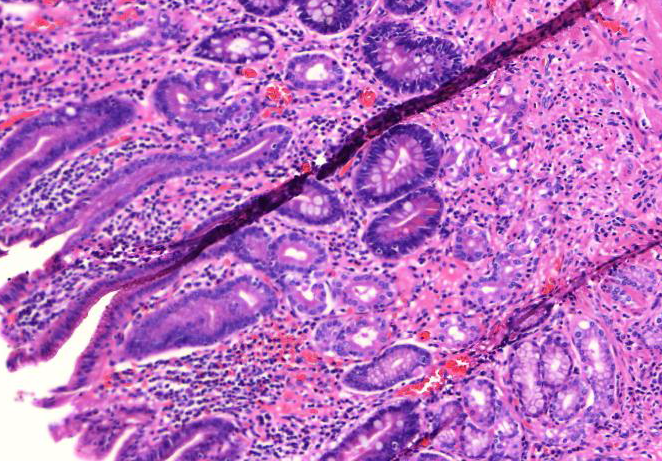

2. Esôfago de Barrett (A521)

1. Epitélio

1. Espessado

1. Presença de células colunares

1. Glândulas mucosas

1. Metaplasia intestinal

2. Camada basal hiperplásica

1. Células basais mais esculas

3. Submucosa inalterada